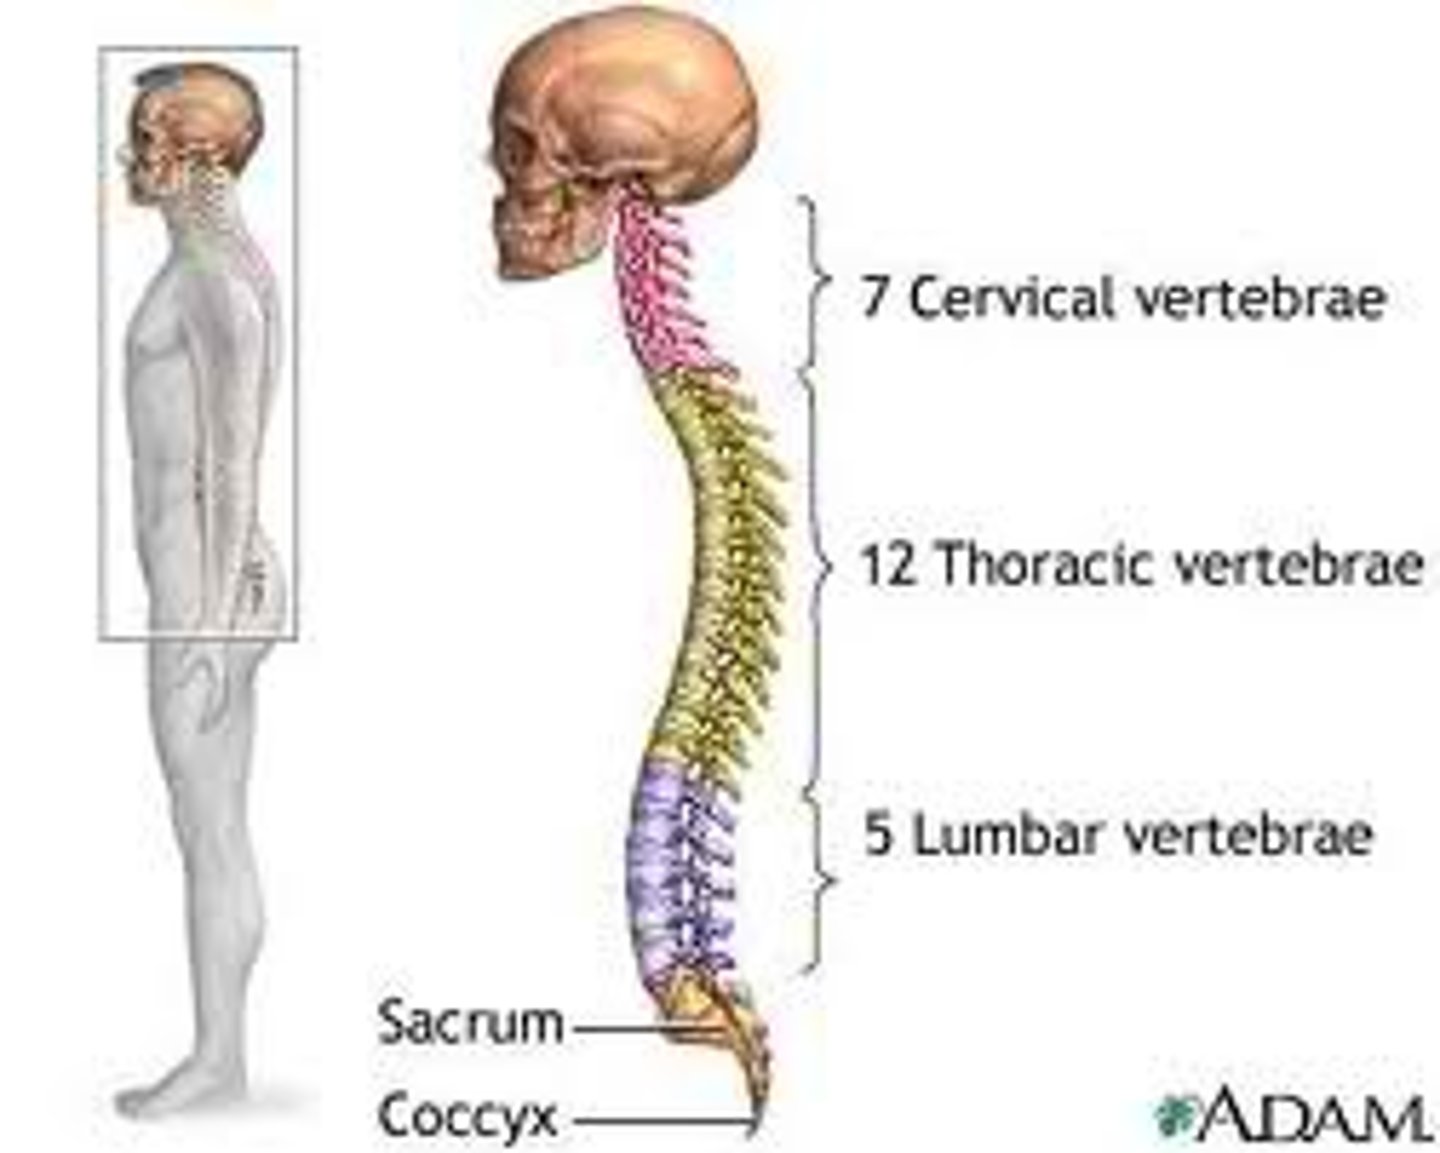

What are the sections of the vertebral column?

cervical, thoracic, lumbar, sacrum, coccyx

How many vertebrae make up the cervical spine?

7

How many vertebrae make up the thoracic spine?

12

How many vertebrae make up the lumbar spine?

5

Which regions of the spine have CONCAVE curvatures and are described as LORDOTIC?

cervical and lumbar

Which regions of the spine have CONVEX curvatures and are described as KYPHOTIC?

thoracic and sacral